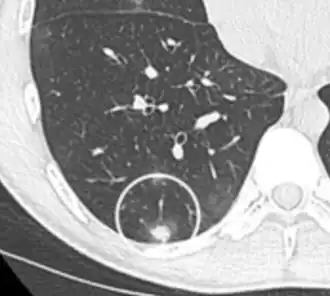

Calcifications and popcorn-like appearance, conferring a diagnosis of hamartoma.[9]

• In case of calcifications, a popcorn-like appearance indicates a hamartoma, which is benign.[3]